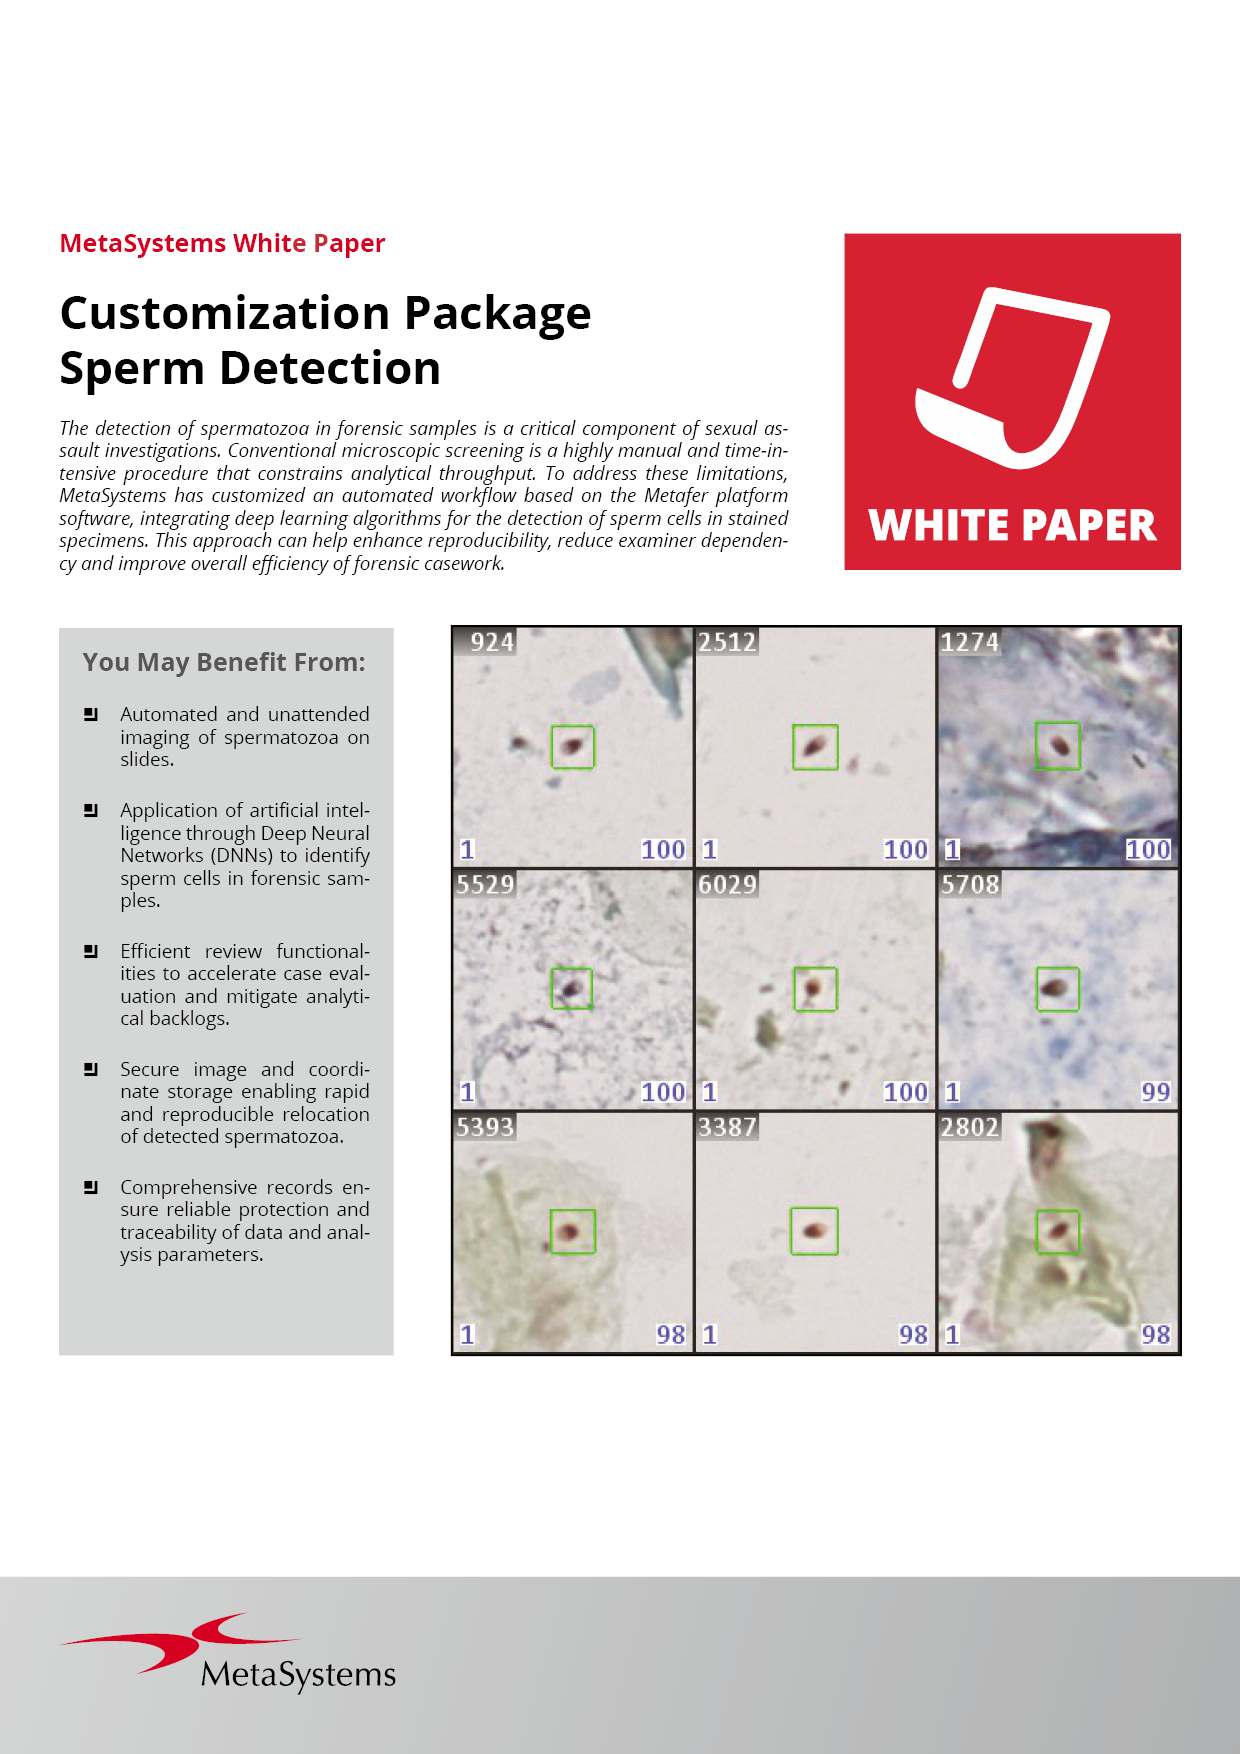

Metafer’s classifier system brings smart automation to object recognition. Combining advanced algorithms with user-defined criteria, it lets users categorize samples quickly while keeping workflows consistent and reliable. With integrated Deep Neural Networks (DNN), Metafer handles diverse sample types with precision, flexibility, and intelligence.

Customization Packages

To help you get the most out of this modular workflow approach, our Customization Packages offer more than a standard setup: they deliver a comprehensive service for configuring Metafer precisely to your task. Drawing on extensive experience from similar installations, our application specialists work closely with your team to define and refine the optimal workflow for your laboratory. This expert support accelerates the path from installation to user validation and routine operation, ensuring a faster, more confident start.

MetaSystems offers Customization Packages for application workflows that have been successfully implemented for customer labs using standard Metafer platform functionality. It is expected that they can be implemented for other customer labs using similar workflows and slide preparation procedures. If a Customization Package is purchased, MetaSystems product specialists will – based on their experience from other similar application cases - support the customer lab in adapting the Metafer software configuration to their needs. The performance of the solution will depend on the quality of the customer slides and the expertise of the users, MetaSystems cannot specify or guarantee any performance parameters. The validation of the solution for clinical use is the sole responsibility of the customer lab.